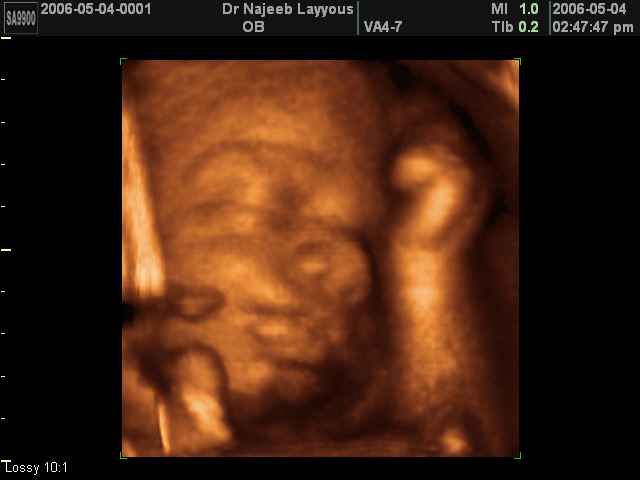

- صور لوجه الجنين في داخل الرحم

- صور لتصرفات الجنين داخل الرحم

صور لتصرفات الجنين داخل الرحم بجهاز الالتراساوند ثلاثي الأبعاد | الدكتور نجيب ليوس